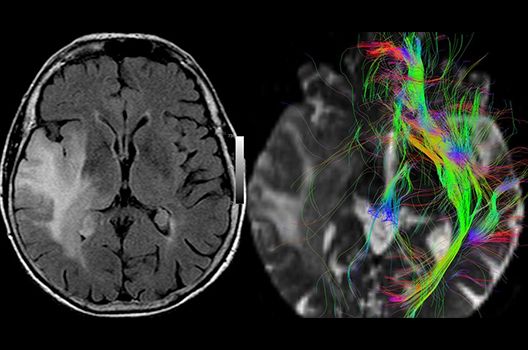

- MR-Diffusionstensorbildgebung (Faserbahndarstellung/fiber tracking)

Die Magnetresonanztomographie (MRT) ist ein Verfahren, bei dem durch magnetische Kräfte Bilder des Körperinneren angefertigt werden. In der Neuroradiologie können manchmal kleinste Veränderungen schwere Folgen haben; daher forschen wir an der Entwicklung hochauflösender MRT-Sequenzen, mit denen diese Prozesse und auch einzelne Nervenfaserbahnen sichtbar gemacht werden können. Darüber hinaus sind bei vielen Erkrankungen des Gehirns die Blutgefäße betroffen. Daher arbeiten wir an der Neu- und Weiterentwicklung von MRT-Sequenzen zur Darstellung der Blutgefäße und zur Blutflussanalyse (sog. „Angio-MRT“). Einen besonderen Forschungsschwerpunkt unserer Klinik stellen die MR-Protonenspektroskopie und die funktionelle MRT dar, mit denen die Analyse einzelner chemischer Substanzen im Hirngewebe oder die Darstellung ausgewählter Hirnfunktionen möglich ist.

Zudem ist das Universitätsklinikum Tübingen das erste Zentrum Europas mit einem deckenmontierten intraoperativen Hochfeld-Magnetresonanztomographen, mit dem bereits während einer Hirnoperation MRT-Bilder angefertigt und ausgewertet werden können. In enger Kooperation mit der hiesigen Neurochirurgie können wir somit zu nahezu jedem Zeitpunkt der OP die genaue Lagebeziehung zu wichtigen anatomischen Strukturen darstellen und das Resektionsausmaß überprüfen.